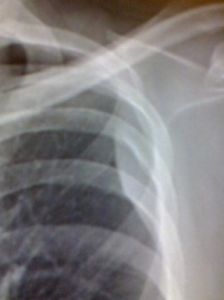

1.局限型者可無明顯不適或僅有胸痛、活動後氣促。2.瀰漫型者有較劇烈胸痛、氣促、消瘦等。3.患側胸廓活動受限,飽滿,叩診濁音,呼吸音減低或消失。4.可有鎖骨上窩及腋下淋巴結腫大。診斷依據

1.胸痛、氣促、消瘦等症狀。2.胸腔積液及胸膜增厚體徵。3.胸片或胸部CT見胸膜結節影。4.胸腔鏡檢查可見結節,並可鉗取活動組織明確病因診斷。預防常識